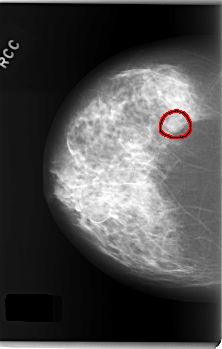

FILE: C_0243_1.RIGHT_CC.OVERLAY

TOTAL_ABNORMALITIES 1

ABNORMALITY 1

LESION_TYPE MASS SHAPE OVAL MARGINS CIRCUMSCRIBED

ASSESSMENT 4

SUBTLETY 5

PATHOLOGY BENIGN

TOTAL_OUTLINES 1

BOUNDARY